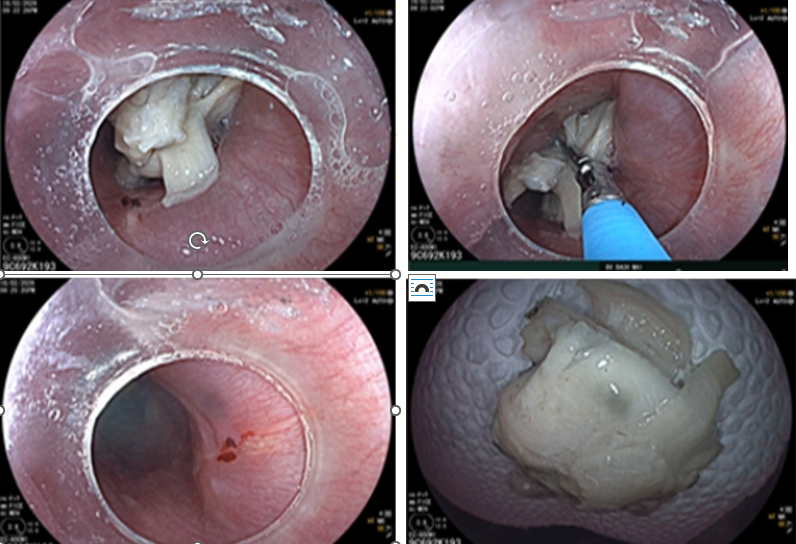

After eating chicken meat, Mr. H.V.Q (66, from Son La) felt pain and a foreign body sensation in his throat, yet assumed it was a minor stuck bone. One day later, when symptoms had not improved, he was transferred to Bach Mai Hospital. A CT scan showed a nearly 3 cm chicken bone lodged across his esophagus, possibly injuring the esophageal wall.

Endoscopy showed the chicken bone embedded in the esophageal mucosa with a small tear.

Fortunately, the object was removed in time. According to Prof. Dr. Nguyễn Công Long – Director of the Gastroenterology and Hepatology Center, if treatment is delayed, a sharp bone could perforate the esophagus and lead to severe infection in the mediastinum — a serious complication that is difficult to treat.

3. 74-year-old woman: Choking on bamboo shoot

Mrs. V.T.N (74, Hanoi) experienced severe choking after eating bamboo shoots during a New Year feast. Thinking the episode was temporary, she tried folk remedies — drinking lots of water, eating more rice, or vegetables — none of which helped.

Food stuck in the esophagus as seen on endoscopy.

Endoscopy revealed the food was stuck in her esophagus and it was successfully removed. In elderly people, swallowing reflexes are weaker and chewing ability may be reduced. Tough or fibrous foods like bamboo shoots, meat, or poultry can easily become lodged if not cut into small pieces and chewed thoroughly.